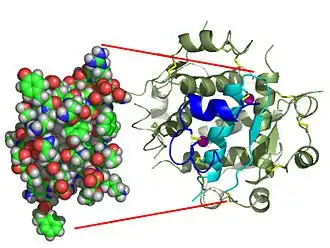

| Monomère d'insuline humaine (PDB 1AI0). | |

L'insuline est une hormone constituée de 2 chaînes polypeptidiques reliées entre elles par 2 ponts disulfures et 1 pont disulfure intrachaîne dans la chaine A : une chaîne A de 21 acides aminés, et une chaîne B de 30 acides aminés. La structure de l'insuline a été déterminée par Frederick Sanger. Ce fut l'objet du premier de ses deux prix Nobel, en 1958. La structure de molécules de plus en plus complexes peut être analysée, jusqu'à ce que, grâce à ses travaux sur la détermination par les techniques des rayons X Dorothy Crowfoot Hodgkin résolve enfin la structure de l'insuline, ce qui lui vaudra le prix Nobel de Chimie en 1969. L'insuline est produite par les cellules β des îlots de Langerhans du pancréas sous la forme d'une pré-pro-insuline constituée d'une seule chaîne peptidique, dont deux fragments, le peptide signal (23AA N-ter) est éliminé par l'action d'une enzyme, la signal peptidase qui va cliver le peptide signal entraînant la création des trois ponts disulfures, on obtient la pro-insuline qui subira l'élimination du peptide C par une autre enzyme, la PC1, ce qui va libérer un fragment central, tandis que les deux chaînes néoformées vont rester associées grâce aux ponts disulfures : enfin l'extrémité C-Terminale d'une des chaines va être clivée par l'action d'une carboxypeptidase E (CPE) pour devenir l'insuline sous sa forme mature, et donc active. La proinsuline a une structure très voisine de celle des deux principaux facteurs de croissance, IGF-1 et IGF-2, et des concentrations élevées de ces hormones permettent des effets biologiques par signalisation après liaison aux récepteurs des autres : hypoglycémie lors de sécrétion massive d'IGF-1 et d'IGF-2 par des tumeurs. L'insuline circule à des concentrations de l'ordre de la nanomole par litre.